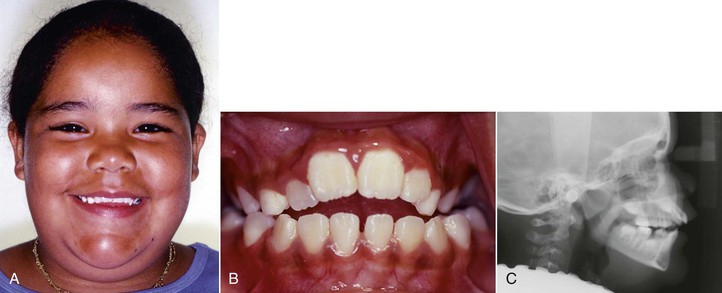

Clinicians should carefully consider the role that the tongue plays in the etiology of open bite. Both the function and the anatomy of the tongue must be evaluated. From an anatomic point of view, a large tongue (macroglossia) can be responsible for splaying the anterior teeth and thus cause an open bite. Unfortunately, macroglossia is difficult to diagnose because no simple method is available to measure the volume of the tongue.44 Certain features noted during clinical examination that indicate macroglossia include spacing and flaring of the anterior teeth, indentations on the lateral borders of the tongue, and lateral extension of the tongue onto the occlusal surface of the lower teeth45 (Fig. 9-6).

Figure 9-6 Patient with a large tongue. A, Intraoral clinical exam shows indentations on the lateral borders of the tongue and coverage of the occlusal surfaces of all lower teeth. B and C, Upper and lower arches depict generalized spacing.